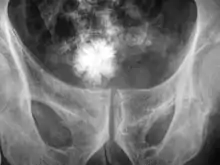

A star-shaped Jackstone urolith can be seen in the urinary bladder on this radiograph of the pelvis

Jackstone calculus

Jackstone calculi are rare bladder stones that have an appearance resembling toy jacks. They are almost always composed of calcium oxalate dihydrate and consist of a dense central core and radiating spicules. They are typically light brown with dark patches and are usually formed in the urinary bladder and rarely in the upper urinary tract. Their appearance on plain radiographs and computed tomography in human patients is usually easily recognizable. Jackstones often must be removed via cystolithotomy.[10]